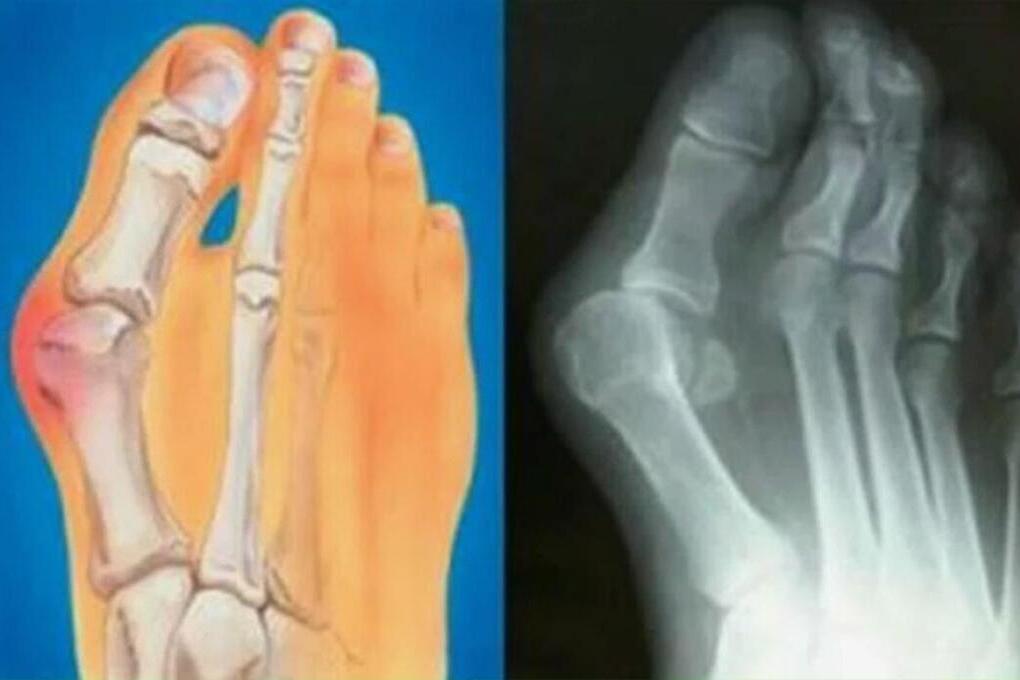

Многим знакома проблема болезненной «шишки» у основания большого пальца стопы. Она мешает ходить, портит обувь и со временем вызывает постоянную боль. Как объяснил травматолог-ортопед ММЦ имени Н. И. Пирогова ФМБА России Виктор Самодолов, причина кроется не в самой «косточке», а в вальгусной деформации стопы.

При этой патологии стопа распластывается, первый палец отклоняется в сторону, а организм формирует костное разрастание для дополнительной опоры. Ранее проблему связывали с каблуками и нагрузками, однако сегодня доказано, что чаще всего она обусловлена наследственностью и передается по женской линии.